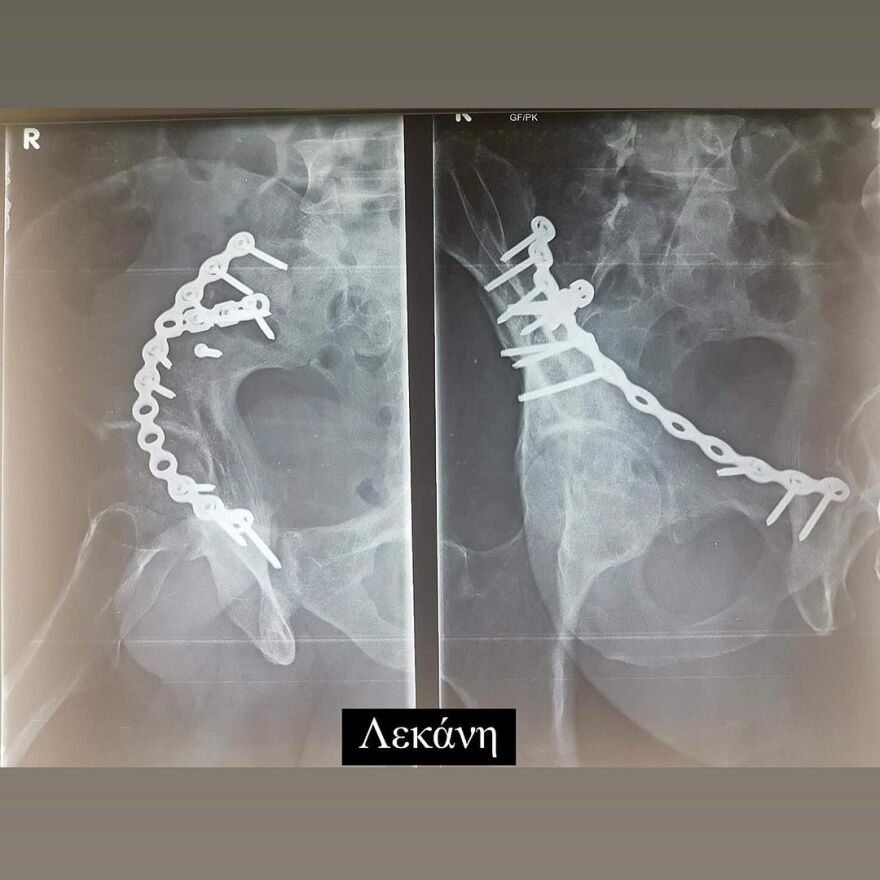

Έδειξε για πρώτη φορά τις ακτινογραφίες με τις λάμες, που έχουν τοποθετηθεί στο σώμα του μετά το ατύχημα

Σε ανάρτηση που έκανε στον προσωπικό του λογαριασμό στο Instagram, ο Ηλίας Βρεττός έδειξε στους διαδικτυακούς του φίλους τις λάμες που έχει στο σώμα του.

Συγκεκριμένα, δημοσίευσε μια σειρά από φωτογραφίες με τις ακτινογραφίες που έκανε. Σε αυτές φαίνονται οι λάμες στο χέρι, το πόδι και τη λεκάνη του.

Στη λεζάντα της ανάρτησής του έγραψε: «19/02 Αγία Φιλοθέη μου Μεγάλη η Χάρη σου!!! Σ´ευχαριστώ… 6 χρόνια πέρασαν και όλα ακόμα μοιάζουν σαν χθες… Τα σίδερα μέσα μου που για πρώτη φορα σας δείχνω στα X-rays έτσι κι αλλιώς δεν με αφήνουν να ξεχαστώ. Όμως είμαι καλά και κυρίως είμαι εδώ! Ο λόγος που το κάνω αυτό είναι γιατί κάθε χρόνο τέτοια μέρα με πιάνουν τα φιλοσοφικά μου και προσπαθώ να ξορκίσω το κακό».